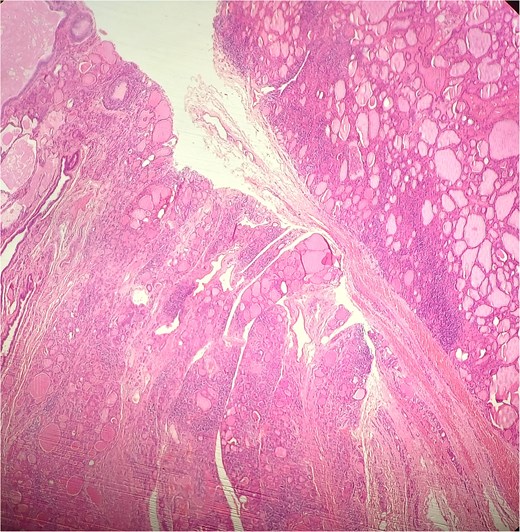

A 47-year-old woman with unremarkable medical history, presented with a 2 months history of neck mass along the midline. Physical examination revealed a 6 cm mobile, thyroid nodule without compressive symptoms. There was no associated erythema, fluctuance, tenderness or adhesion to adjacent structures. There was also no associated cervical lymphadenopathy. The rest of the physical exam was unremarkable. Laboratory tests including TSH, FT3, and FT4 revealed normal levels. On cervical ultrasound, there were a 62 mm left toto-lobar nodule classified as EU-TIRADS3, and an 11 mm right nodule, also classified as EU-TIRADS3. Fine-needle aspiration cytology concluded to a benign lesion classified as BETHESDA II. The patient reported respiratory discomfort in the supine position, leading to the indication for a lobectomy. Gross examination of the specimen revealed a toto-lobular nodule with a colloid appearance. It was well-circumscribed by a thin and regular fibrous capsule. The nodule measured 4 × 6 cm and exhibited areas of fibrous, whitish remodeling, as well as hemorrhagic and cystic changes. On microscopic examination, the nodule corresponded to a macro vesicular adenoma altered by fibrosis and hemorrhage. It was surrounded by a thin, regular, and intact fibrous capsule. However, at the periphery of the nodule, adjacent to the thyroid pseudo capsule, a 1.2 cm cystic ductal structure was observed. It showed pseudostratified ciliated columnar and squamous epithelial lining associated with thyroid follicles in the surrounding stroma (Figs 1 and 2). These thyroid follicles were bland with no papillary nuclear atypia or invasion (Fig. 3). The cyst was filled with a thin eosinophilic material (Fig. 4) Lymphocytic thyroiditis of mild severity was identified in the rest of the thyroid tissue. Based on these findings, the diagnosis of macro vesicular thyroid adenoma with ITTGDC and lymphocytic thyroiditis was made. After the surgery, the patient developed temporary dysphonia.